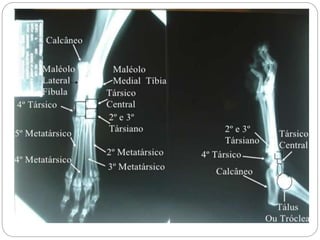

Figura – 2

Dorso-ventral